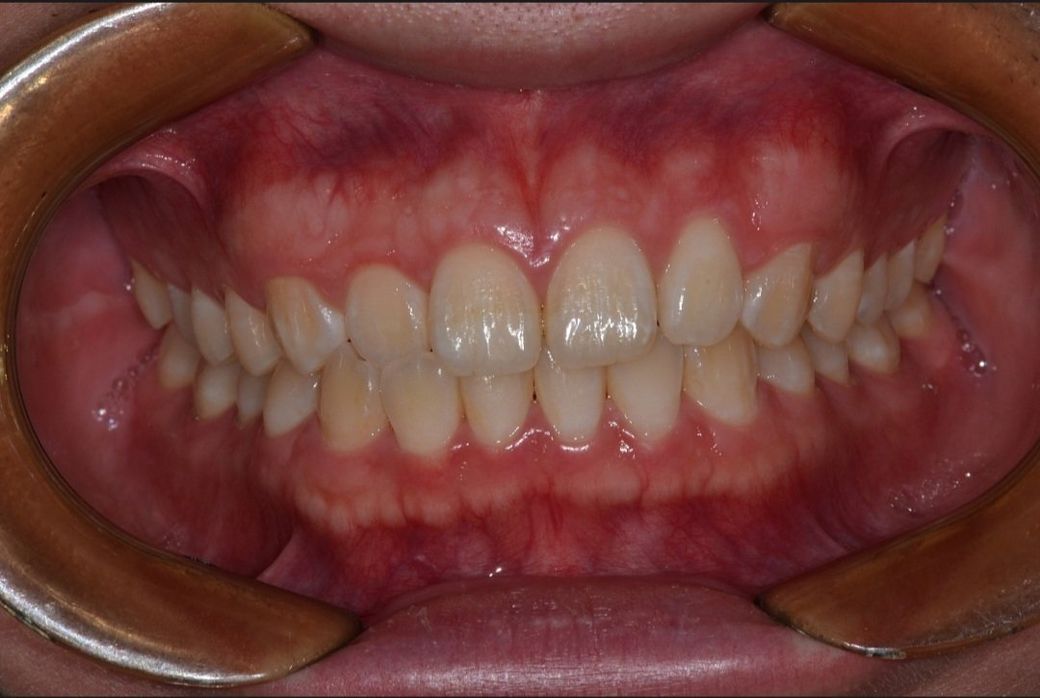

• 2번 째 사진

일단 현재 말씀하시는 증상은 사진 자료로는 판단하기 힘듭니다. 교합지 등으로 교합을 검사해야 하며 단순히 사진 자료로는 알기 힘듭니다. 또한 지금 안모 사진으로 보았을 때는 비대칭이 심하지 않으며 지금과 같은 비대칭은 정상범주에 속합니다.

또한 사람들마다 정중선이 완전히 일치하는 경우는 거의 없으며 정상 범주에 있다면 교정을 통해 무리하게 개선하지 않습니다.

사진상으로는 정확히 판별할수는 없습니다. 다만 사진으로 보면 크게 교합에는 문제가 없는거 같으며 한쪽이 깊게 물려서 그럴수도 있을것같습니다. 특별한 부위가 깊게 물려서 치아가 예민해지고 불편감을 느끼시는거 같습니다. 아래 ct사진으로 보면 얼굴에 약간의 비대칭이 존재하는거 같으며 치아의 흰색은 치아가 부식된부분입니다